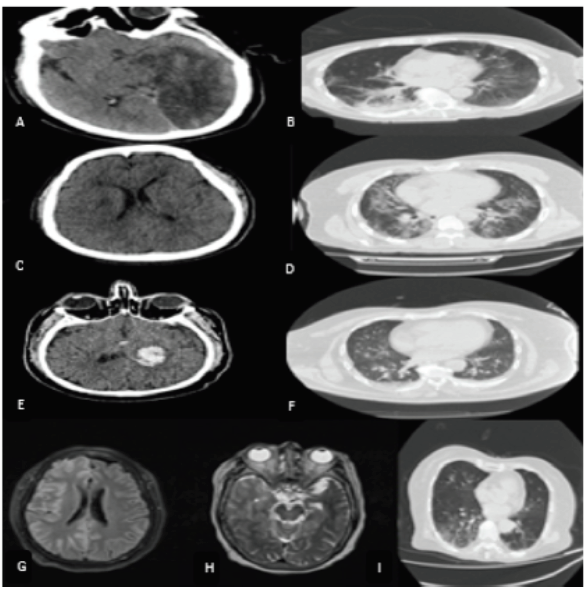

En relación al ACV Isquémico, el porcentaje fue de 2,7%, en comparación a otros reportes de países europeos (Italia, Francia y Holanda), 1 de Asia (china) y 1 de América, donde describen entre 0,9% a 2,7%(10,16–20), La mediana para la edad fue 69 años, estos datos no están lejos de lo publicado en una reciente revisión sistemática que incluye 135 pacientes (promedio de 63 años)(19); además casos en adultos jóvenes también han sido descritos (20,21) al igual que en nuestro estudio (20,21). La mayoría de los pacientes de nuestro estudio (93%) tuvieron un ACV isquémico moderado a severo según el puntaje de NIHSS, que estaría en relación con lo publicado recientemente, en donde se describe en un análisis comparativo, que los pacientes con COVID-19 sufrieron ACV más graves, con una puntuación NIHSS más alta y una mayor mortalidad hospitalaria, a diferencia de los pacientes COVID-19 negativos o controles históricos. El 3% recibió trombólisis, cifra que resulta ser baja comparado con lo reportado en otros estudios que alcanza el 33,7%.Además la mortalidad en este patología es alta, en nuestro estudio fue 33% similar a lo descrito en una revisión sistemática que alcanza el 38% (16,19-21). La concurrencia entre ACV isquémico e infección por SARS-CoV-2 se ha ido reportando con el pasar de los meses desde que inicio la pandemia, si bien es cierto ambas entidades nosológicas comparten factores de riesgo, la infección por SARS-CoV-2 podría ser un desencadenante, se postulan diversos mecanismos de causalidad, tanto de forma directa e indirecta. La forma directa sería a través del daño de células endoteliales de los vasos arteriales cerebrales pequeños (produciendo infartos lacunares) o vasos de mayor calibre (ocasionando disecciones y por ende infartos cerebrales); el mecanismo indirecto se explica por el estado protrombótico (documentado por el aumento del dímero D, fibrinógeno), estado hiperinflamatorio y además un posible daño miocárdico que condicionaría eventos cardioembolígenos (12,22–24). Hubo limitaciones en la realización de los exámenes de apoyo diagnóstico (figura 1).

Los casos de ACV hemorrágicos a diferencia de los ACV isquémicos han sido menos reportados en pacientes con COVID-19. En nuestra revisión fueron 4 casos. La SEN reportó 4 (4,3%); Mao, describió 1 paciente; Li reportó 1 caso de un total de 11 pacientes (25), Sharifi 1caso (26) y Morassi 2 casos (27). Los pacientes reportados en su mayoría comparten factores de riesgo vascular con la infección por SARS-CoV-2. Además en el contexto de la infección ocurren trastornos de coagulación, plaquetopenia y el síndrome de tormenta de citocinas los cuales también pueden ser factor de riesgo (28,29) (figura1).

En los casos con encefalitis, paciente de sexo femenino, 77años, ingresó con 2 días de disnea y 1 día previo al ingreso a emergencia presentó sopor, hemiplejía izquierda y a los 3d de hospitalizada entró en status convulsivo, líquido cefalorraquídeo (LCR) incoloro transparente, escasa pleocitosis con hiperproteinorraquia y glucosa normal. Resonancia de encéfalo compromiso cortico subcortical a nivel de región frontal derecha en FLAIR, pérdida de la sulcación por engrosamiento de circunvoluciones, sin realce meníngeo al contraste. Falleció a los 9 días (figura 1). Otro paciente de sexo masculino, 53 años, ingresó con 4 días de enfermedad caracterizado por malestar general, dolor faríngeo, tos, fiebre, crisis convulsiva, tomografía cerebral sin contraste tenue hipodensidad frontal izquierda, LCR sin pleocitosis, con hiperproteinorraquia y glucosa normal, falleció a los 9 días.